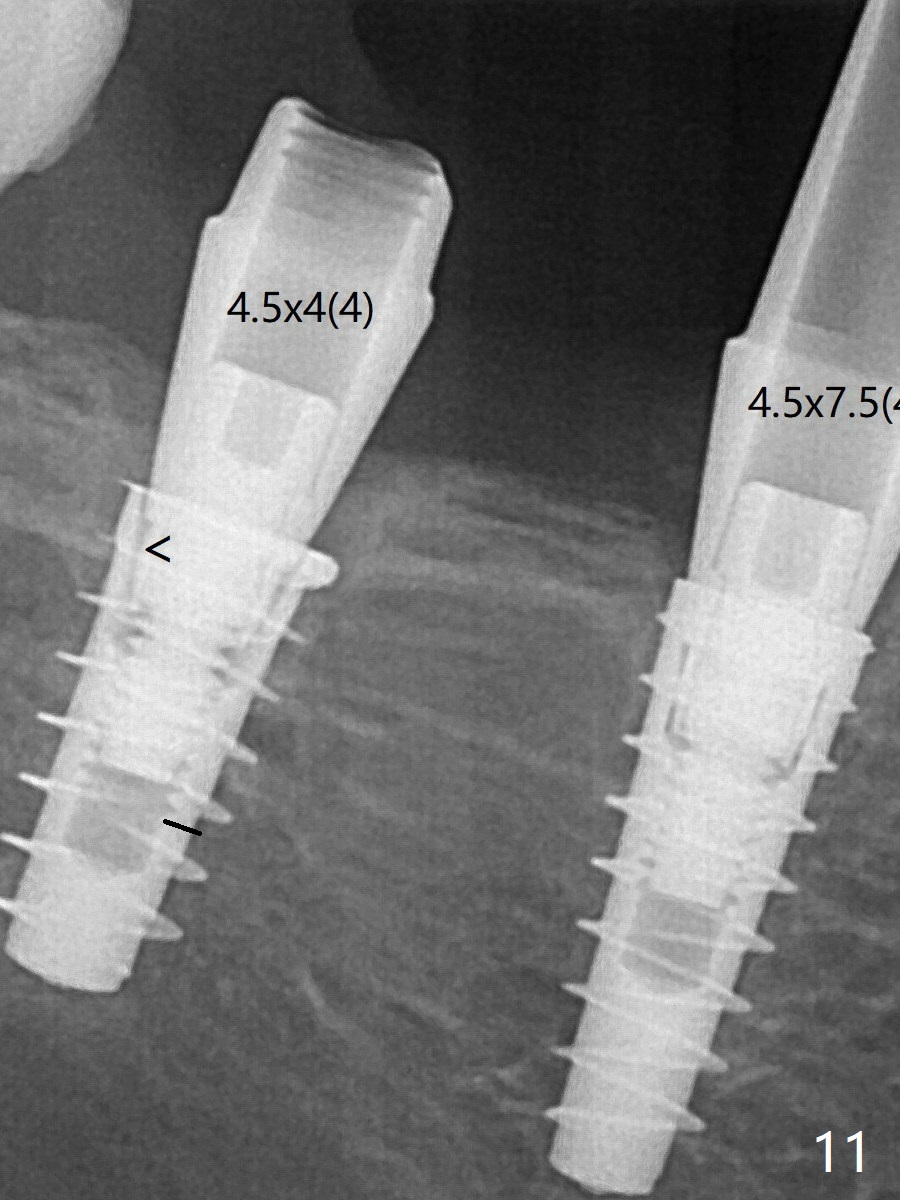

通过旋转7 基台,终于就位(图十二:箭头),螺丝往下移位(与图十一:横线对比),但是基台边缘太低,不利于取模。